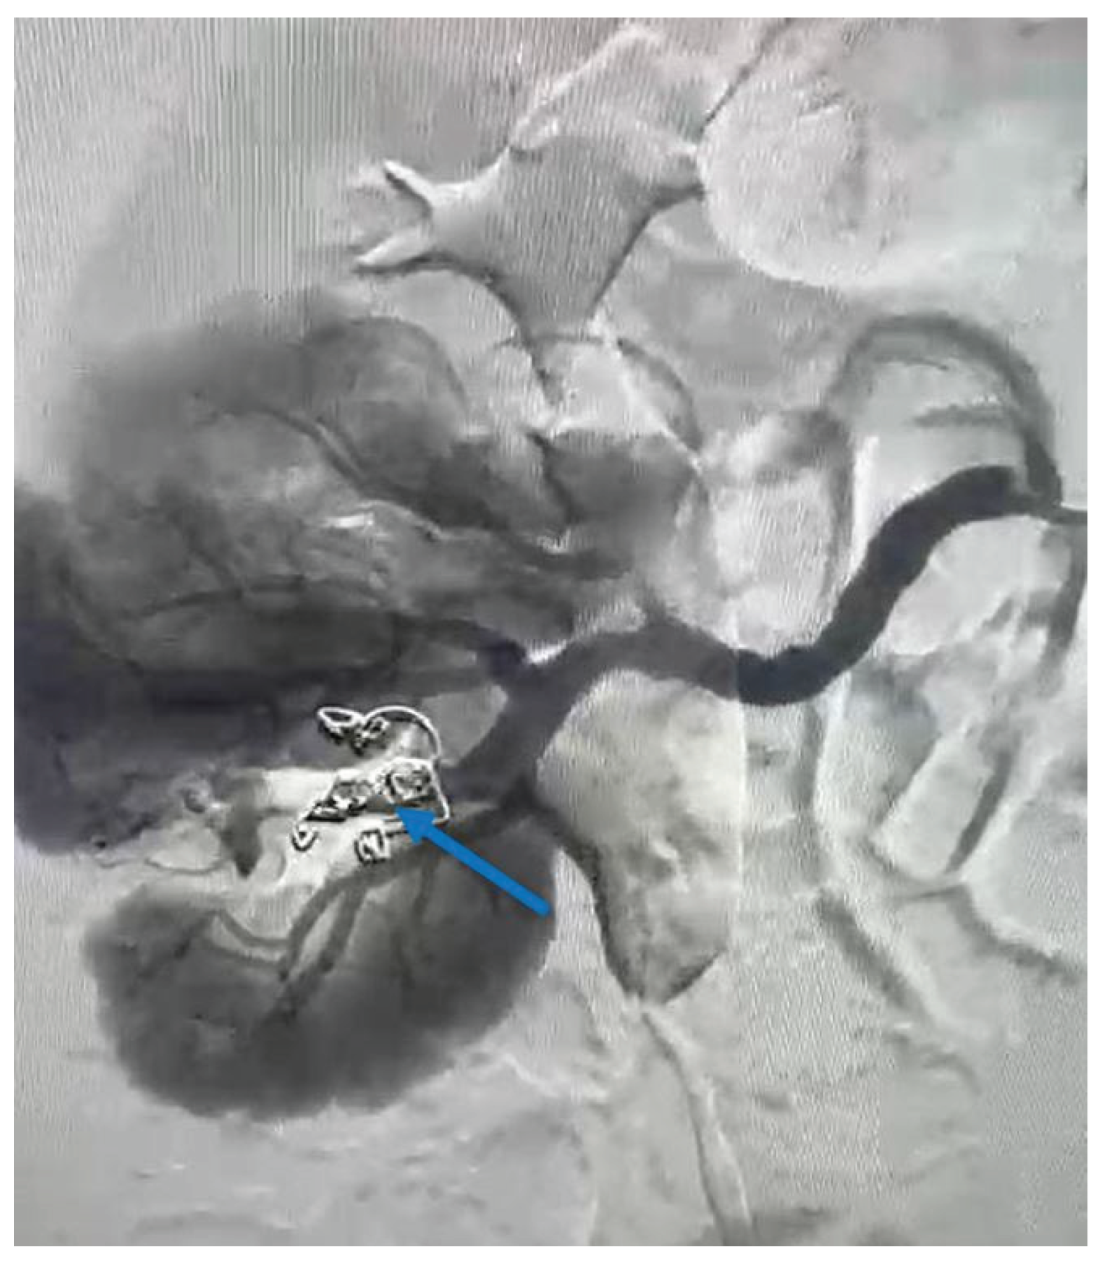

To control and cease the hemorrhage, a guidewire was introduced at the vessel’s site, and a selective embolization was carried out using two VortX Diamond© coils of 6/7.7mm each (Figure 4). The procedure time of the angioembolization was 7 minutes and 50 seconds.

The renal haemorrhage can be controlled using various embolic agents, although some studies underline the higher effectiveness of coils in several clinical situations [19,20,23,24,25,26]. The main reasons discussed include the facile manipulation, lower rates and smaller areas of renal ischemia—therefore a lower degree of renal function impairment —and better tracking accuracy of the embolic agent after its detachment into the target vessel [19]. As described and pictured earlier in Figure 4, coils were also used in the present case as an embolic agent during the angioembolization.

Considering the patient’s medical history, which includes a previous selective angioembolization (SAE), our focus shifted toward identifying potential risk factors that may have contributed to or predicted the failure of the procedure. In a study that evaluated the predictive factors of SAE failure for moderate- to high-grade renal trauma, Baboudijian et al. found gross hematuria, hemodynamic instability, and urinary extravasation to be statistically significant [32]. After the first SAE, our patient did not exhibit any of these factors. In a case report published by Seno et al., another set of risk factors was identified as significant in predicting initial super-selective renal arterial embolization failure; this set includes multiple percutaneous access sites, more than two bleeding sites on a renal angiogram, and the use of a gelatin sponge alone as embolic material [3]. In our case, the patient presented with only one percutaneous access site during the initial angioembolization and a single bleeding site on the renal angiogram. During the angioembolization procedure, two coils were used (as depicted in Figure 3 – indicated by the orange arrow). Thus, none of the aforementioned situations were present in our patient’s case.

Figure 4. Angiographic aspect of the right kidney after angioembolization (the blue arrow indicates the VortX Diamond© coils which have been used).